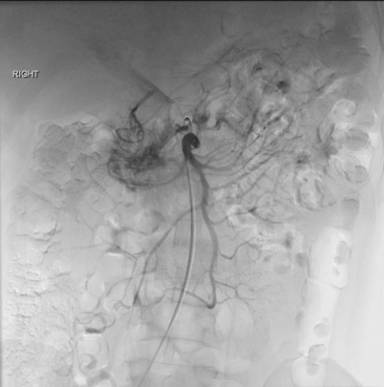

The superior mesenteric angiogram demonstrated significant vascular contribution to the pancreatic head arteriovenous malformation only (Figure 3). The inferior mesenteric artery angiogram showed no vascular contribution.

Figure 3. The superior mesenteric angiogram demonstrating: significant vascular contribution to the pancreatic head arteriovenous malformation only (white arrows). |